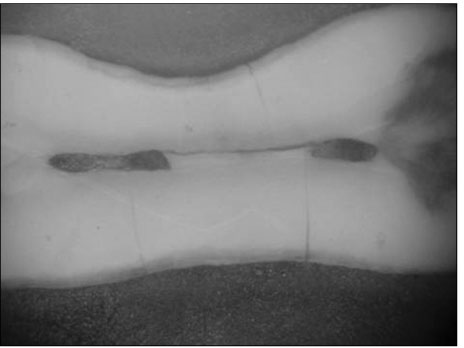

Figure 3

Photograph of section in distal root at 3mm from root apex (×60)

Figure 3 Photograph of section in distal root at 3mm from root apex (×60)